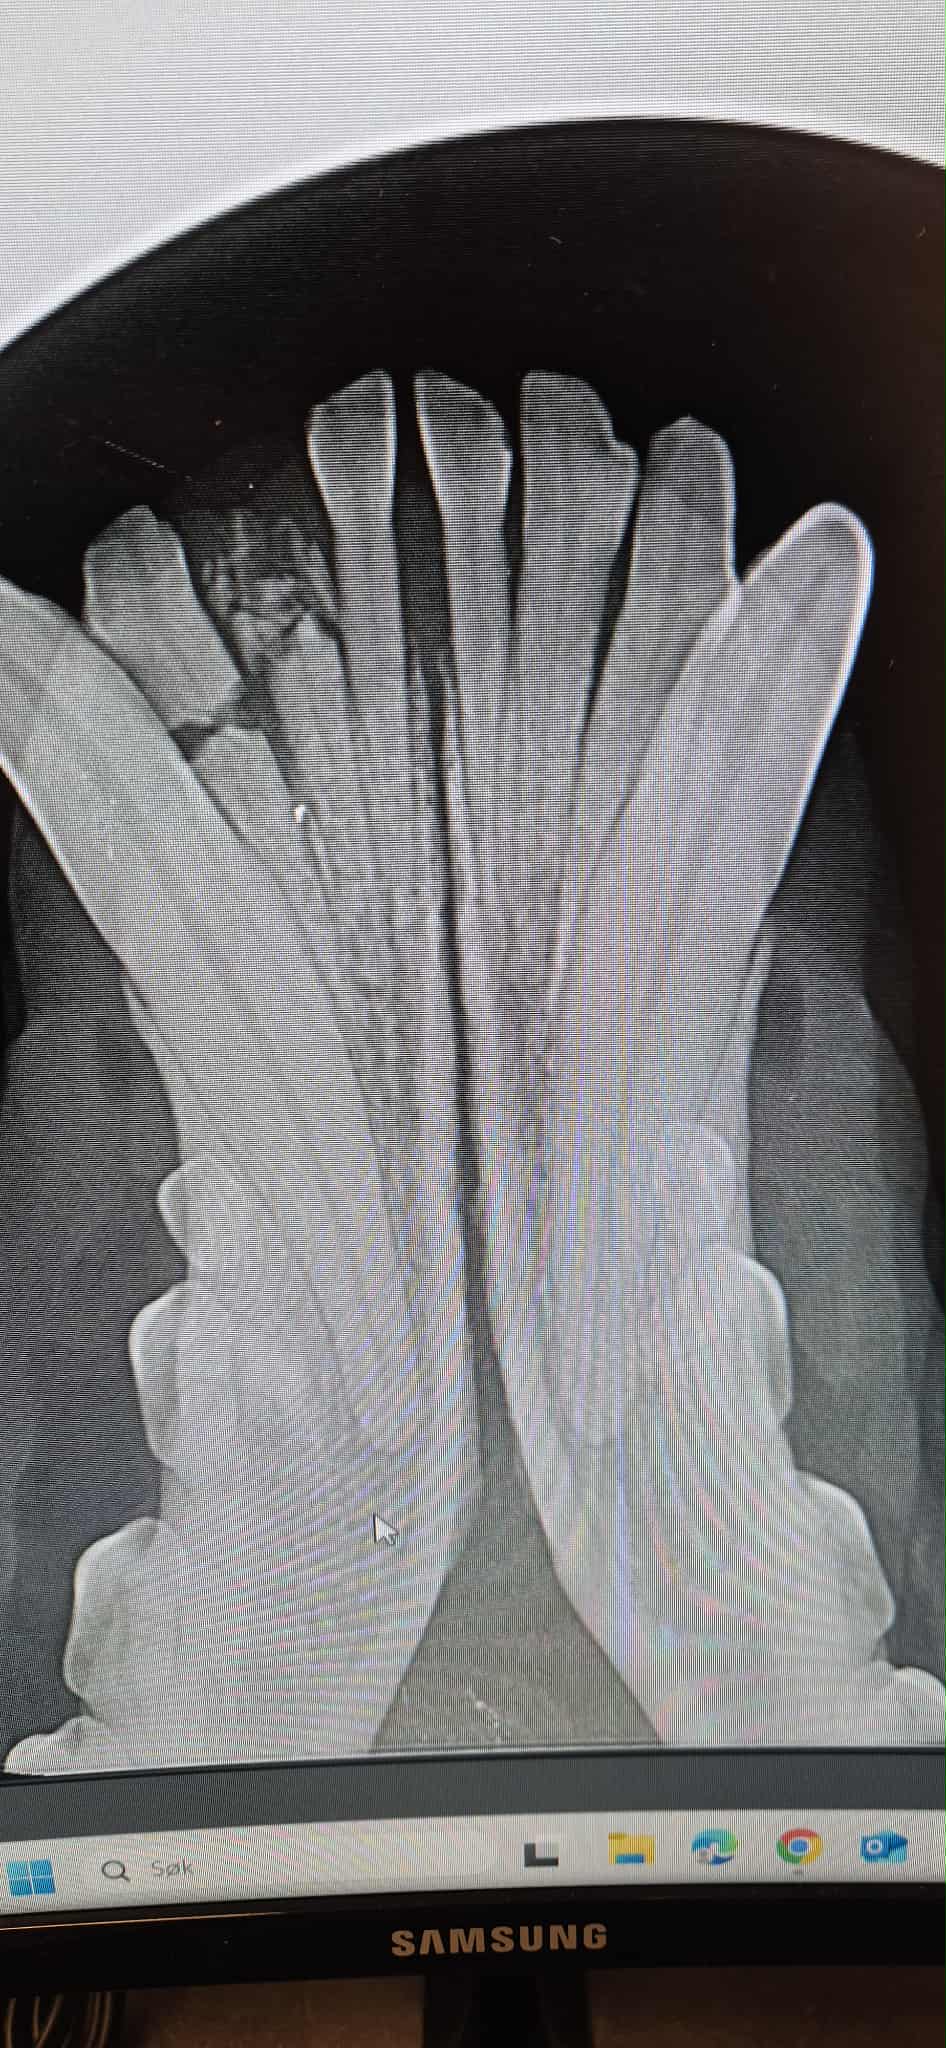

Tannrens hund m/fullstatus røntgen: fra 4000kr (avhenger av størrelse på hund)

Tannrens katt m/fullstatus røntgen: 2850kr